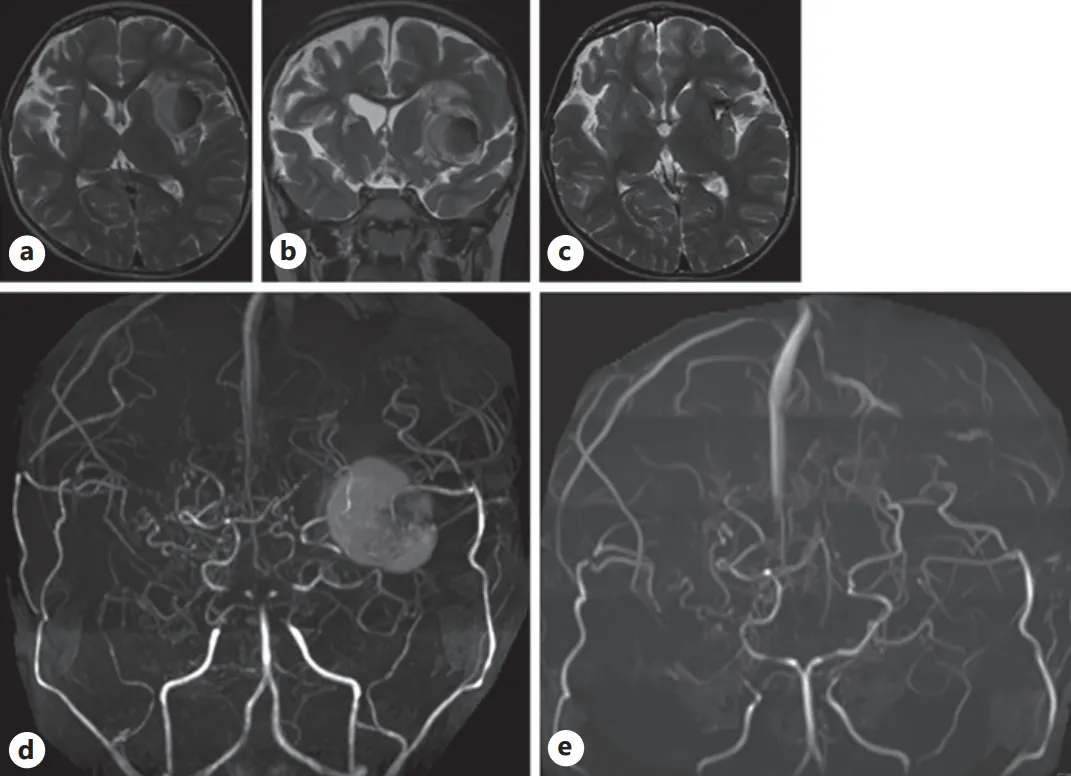

术后一年半常规复查时,发现患儿左脑岛叶存在小病灶,鉴于无症状表现,医疗团队决定谨慎减少阿司匹林剂量并密切观察。一月后病灶扩大并压迫脑组织,虽仍无症状,为防止继续进展压迫脑组织,再次紧急手术清除,发现为"包膜完整的新旧混合血肿",未发现动脉瘤或血管畸形。

随访轴位(a)与冠状位(b)T2加权磁共振成像(MRI)图像:可见左侧岛叶病灶扩大至两倍以上,周围伴水肿组织。

(c)术后T2加权MRI显示原异常病灶被手术疤痕组织取代。

术前(d)与术后(e)磁共振血管造影(MRA):术前MRA较大病灶在术后影像中消失。

此次手术后患儿恢复良好,未遗留任何后遗症。